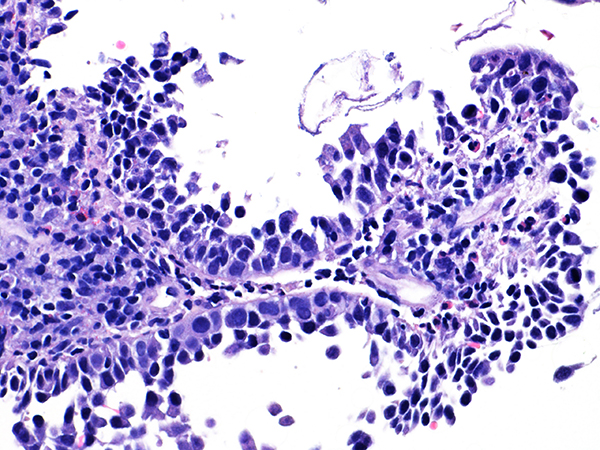

Area 1 - Soft Bx CIN 2 40x - High Power |

![]() Case 1

Area 2 - Soft Bx CIN 2 40x - High Power |